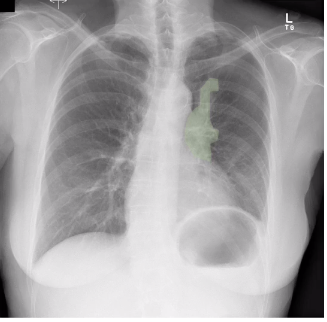

whats this?

cardiopacemaker